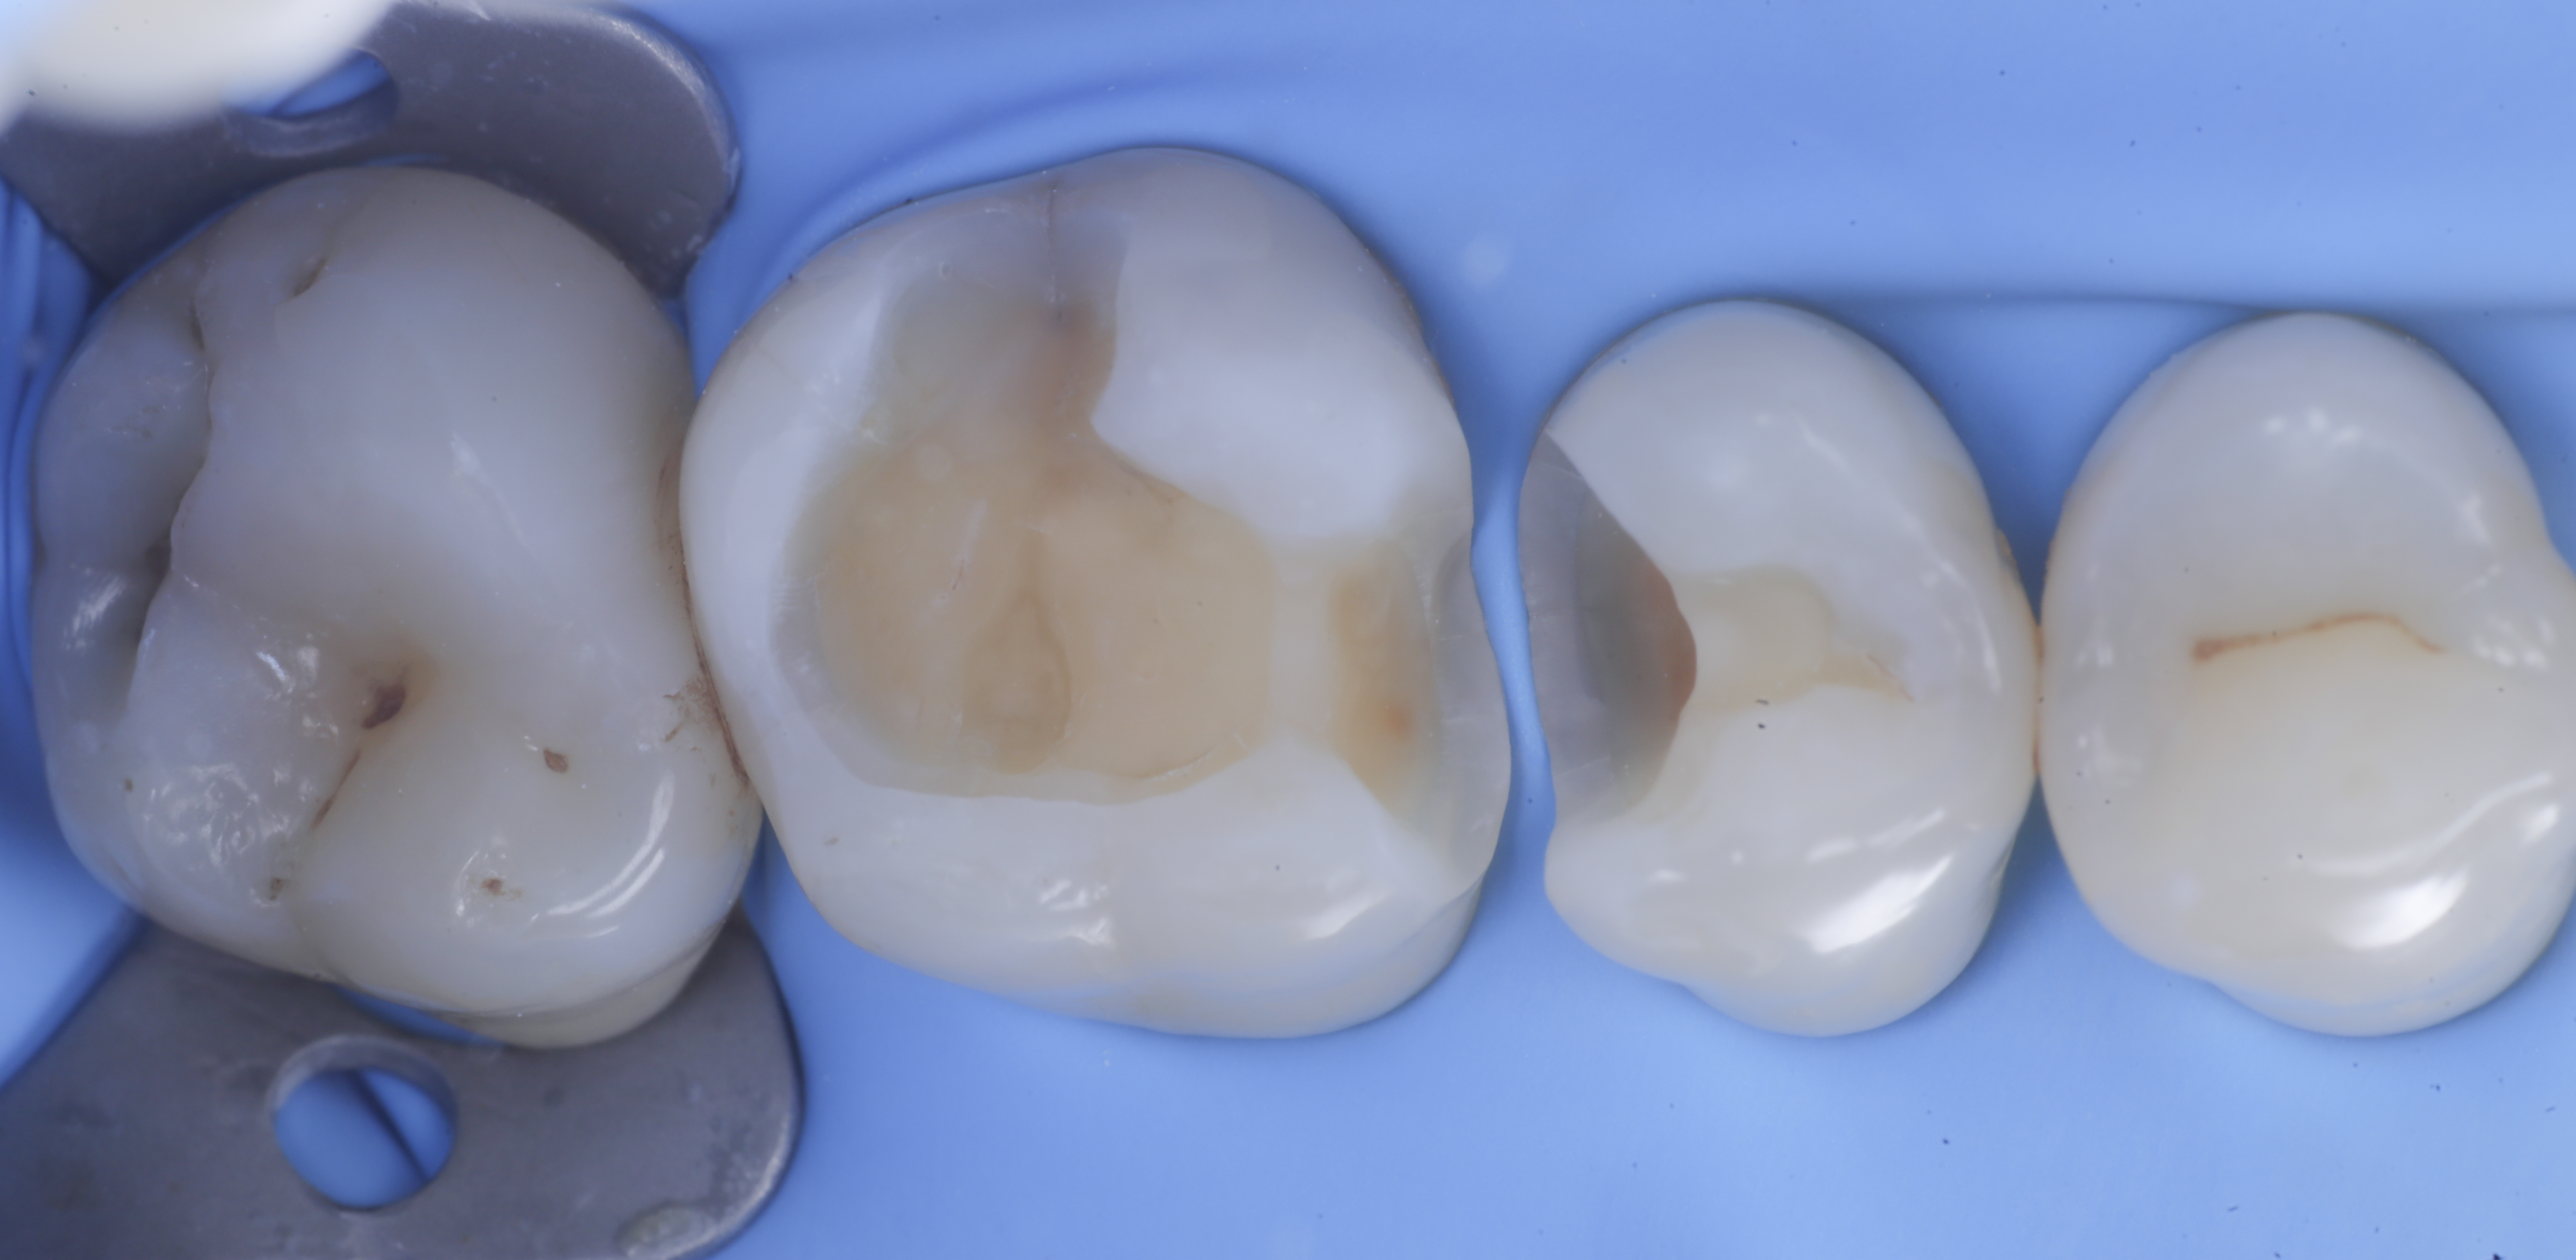

foto 1 Fotografia iniziale

foto 2 Isolamento e aspetto delle cavità ultimate